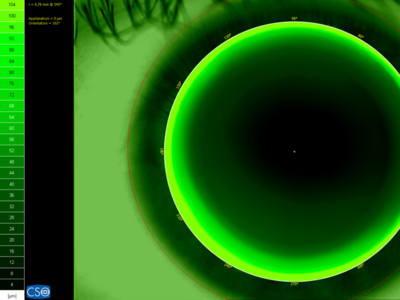

Η τεχνολογική εξέλιξη έχει συμβάλλει ιδιαιτέρως στη διαγνωστική της νόσου αυτής. Συγκεκριμένα, έχει αναπτυχθεί ένα μηχάνημα, ο τοπογράφος κερατοειδούς, ο οποίος λαμβάνει μια ειδική φωτογραφία, η οποία αναλύεται με βάση συγκεκριμένους λογαρίθμους και προκύπτει ένας χάρτης τιμών, ανάλογα με την καμπυλότητα, το σχήμα, το πάχος και τη διαθλαστική ισχύ σε πάνω από 5000 σημεία μέτρησης στην επιφάνεια του κερατοειδούς. Η τοπογραφία επιτρέπει την διάγνωση του κερατόκωνου σε πολύ πρώιμο στάδιο, ακόμα και προτού ο ασθενής ο ίδιος παρατηρήσει οποιοδήποτε σύμπτωμα. Αυτό προσφέρει ένα πολύ σημαντικό πλεονέκτημα, αφού, όσο πιο νωρίς γίνει η διάγνωση της νόσου, τόσο πιο έγκαιρη και αποτελεσματική είναι και η αντιμετώπισή της.

Το οφθαλμολογικό μας κέντρο διαθέτει πλέον την κορυφαία τοπογραφία CSO Antares, με 24 ομόκεντρους δακτυλίους Placido και 6144 σημεία μέτρησης σε κάθε φωτογραφική λήψη του κερατοειδούς. Με τον τρόπο αυτό παρέχουμε στους ασθενείς μας πλήρη εξέταση του κερατοειδούς και δυνατότητα διάγνωσης, αλλά και παρακολούθησης της εξέλιξης του κερατοκώνου με ακρίβεια και άριστη ποιότητα.